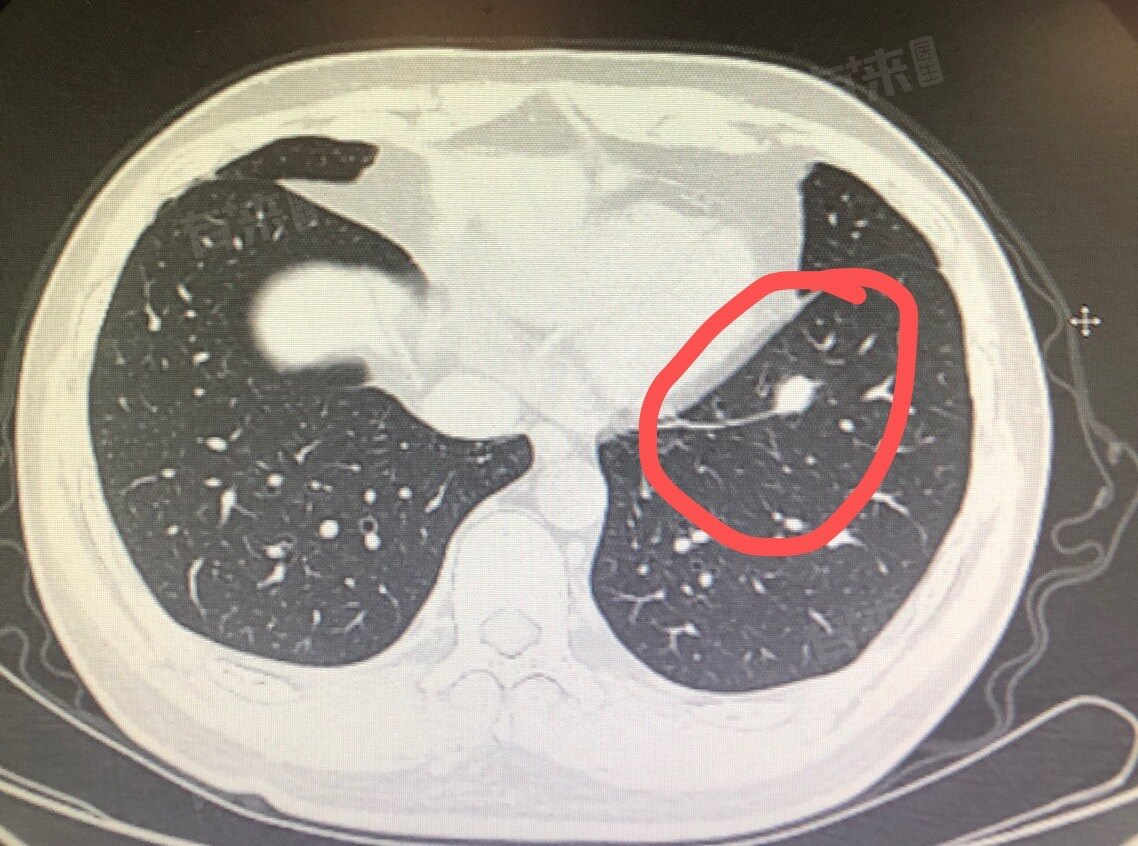

肺结节6×4mm实性结节一般不算严重。6×4mm的实性肺结节属于较小的结节,对于这种大小的实性结节,其良性的可能性相对较大,可能是由于肺部的炎症、感染、陈旧性病变等原因引起的。

- 从结节的形态特征来看,如果结节边缘光滑、规则,没有分叶、毛刺、胸膜牵拉等恶性征象,那么良性的概率就更高。如果患者没有明显的症状,如咳嗽、咳痰、咯血、胸痛、呼吸困难等,也提示结节可能相对比较稳定。

- 对于6×4mm的实性肺结节,一般的处理方法是定期随访观察。首次发现后,可能会建议在3个月、6个月或12个月后复查胸部CT,观察结节的大小、形态、密度等是否有变化。如果在随访过程中,结节没有明显变化,则可以逐渐延长复查的时间间隔。如果结节出现增大、形态改变或出现恶性征象,就需要进一步检查,如增强CT、PET-CT、经皮肺穿刺活检等,以明确结节的性质。